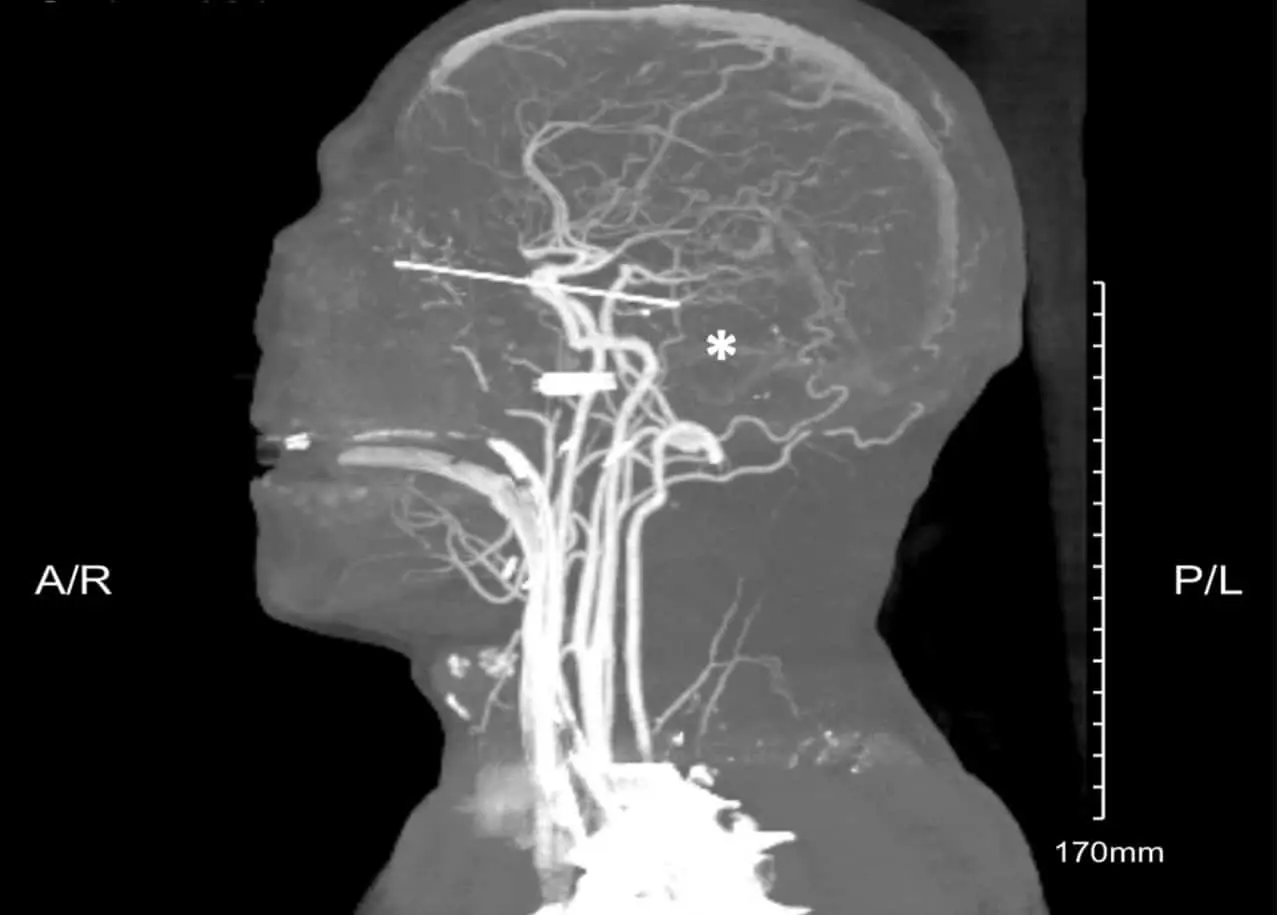

Пациент поступил в отделение неотложной помощи с проникающими ранениями обоих глаз. Результаты томографии показали, что деревянный карандаш глубоко вошел в левую глазницу, повредив зрительный канал, кавернозный синус и достигнув моста головного мозга — критически важной структуры, отвечающей за жизненные функции.

После срочного вызова скорой помощи бригада нейрохирургов и офтальмологов под рентгеноскопическим контролем извлекла инородное тело. Несколько дней врачи боролись за стабилизацию состояния пациента, но развившийся отек мозга, кровотечение и высокое внутричерепное давление привели к необратимым последствиям. На пятые сутки была констатирована смерть мозга.